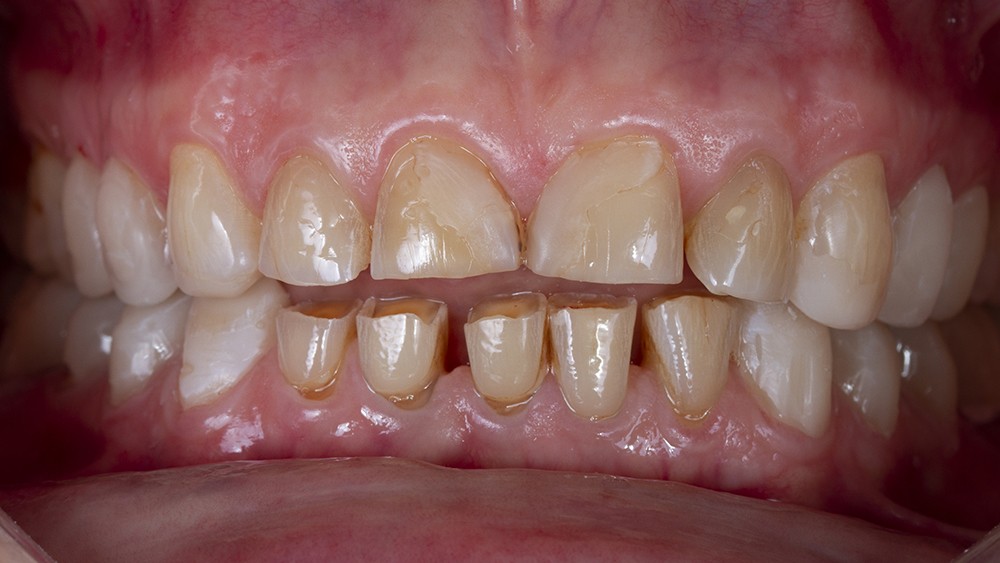

En effet, certaines situations cliniques (perte de dimension verticale et des fonctions masticatoires ou esthétiques) requièrent l’utilisation de matériaux dont la résistance mécanique permet d’envisager une prise en charge globale et pérenne du patient [6]. Ces matériaux (céramiques renforcées ou polymères hybrides) imposent des préparations plus invasives pour répondre aux exigences de résistance mécanique propre à chacun d’eux [7]. Toutefois, afin de minimiser la perte tissulaire, le concept de préparation à travers un mock-up postérieur s’est imposé comme l’option la plus judicieuse [8, 9]. Si la réalisation de ce mock-up peut paraître simple face à une denture naturelle usée de façon homogène, il en est tout autrement lorsque l’usure est irrégulière. Ces situations se rencontrent fréquemment quand le patient est partiellement équipé de restaurations périphériques anciennes ayant engendré des phénomènes d’usure par abrasivité différentielle entre la céramique et l’émail antagoniste.

En outre, l’analyse clinique initiale permet d’appréhender deux situations cliniques très distinctes : la perte de dimension verticale (DVO) ou, au contraire, le maintien de celle-ci par égression compensatrice des dents. De façon très schématique, une usure rapide, de type érosive, entraîne plus facilement une perte de dimension verticale, alors qu’une usure lente permet souvent à l’organisme d’effectuer une égression compensatrice [11].

Enfin, une analyse attentive des courbes d’occlusion est menée, notamment dans les cas d’édentements non compensés ou lorsque des restaurations en céramique sont déjà présentes [12] (fig. 1). En effet, la présence de ces dernières peut entraîner une usure différenciée de la dent naturelle antagoniste.

Ainsi, les usures engendrent, dans la majorité des cas, des perturbations au niveau des courbes d’occlusion, lesquelles devront être corrigées lors de la réalisation du wax-up [13].